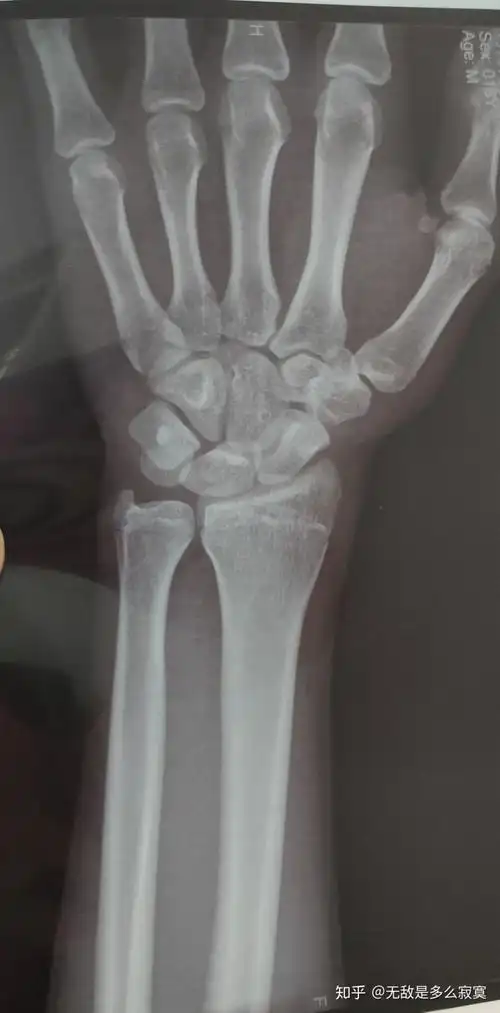

男孩,年龄17岁,去医院测骨密度拍了x光片(如图),请看看骨骼线是否闭合